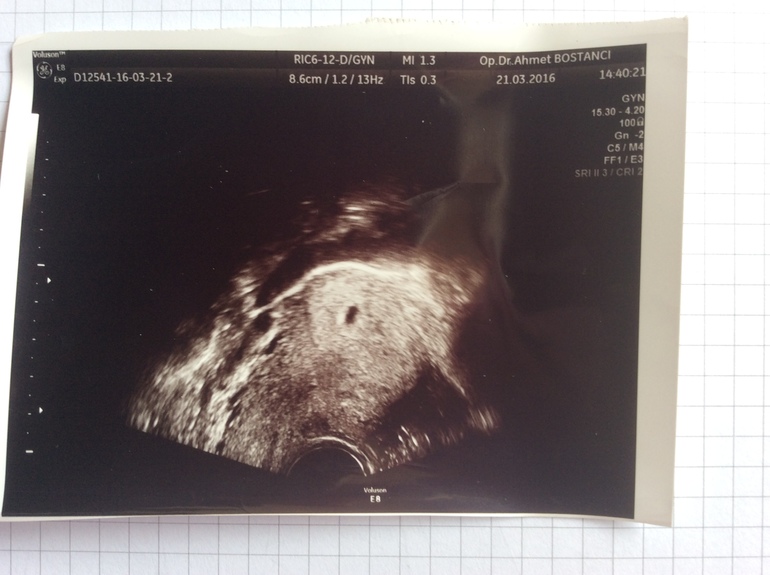

На 4 нед и 3дня на УЗИ уже увидели свою букашечку)) через две недели идём слушать сердцебиение